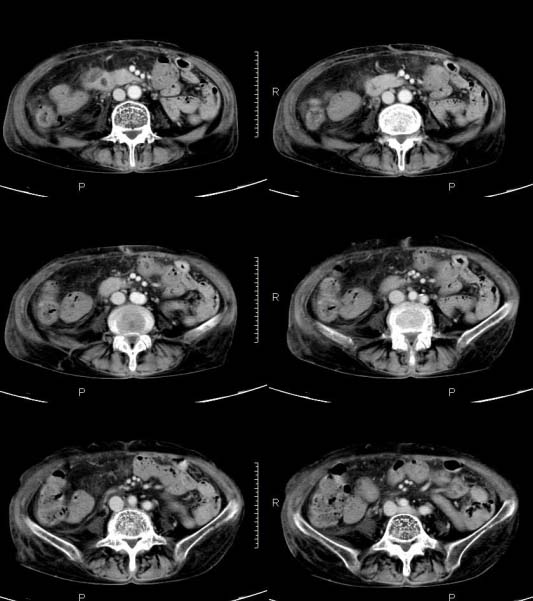

女,71岁,腹痛、腹胀、黄疸20余天,b超示肝内外胆管高度扩张内伴絮状物质(未提示梗阻部位或结石影),经抗炎解痉治疗后,肝功能有所好转,但胆道梗阻状态并未减轻。患者曾于1970年代做过胆囊切除术,1997年因胰腺炎而手术;且患者有糖尿病10余年。ct图片传了静脉期,未传动脉期了,最后一序列为3.2mm薄扫,请各位同仁仔细看看,确定一下胆管梗阻的部位,是炎性梗阻还是肿瘤性梗阻,是否与胰腺炎有关系,扩张胆总管中段前缘是否是胰管。请高手们最好用图示来指出梗阻部位。

扩张的胆管直达胰头,但胰头增大又不明显,且无异常密度影。考虑壶腹部占位。

支持2楼   非梗阻病变    胰管无明显扩张

肝内胆管远侧、近侧不比例扩张,以近侧为明显。胆总管扩张。考虑先天性胆管囊肿(ⅳ型)。